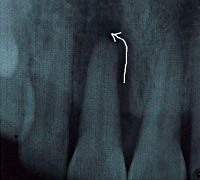

Врач-стоматолог устанавливает диагноз на основании жалоб и характерных симптомов. Рентгенологическая диагностика маргинального периодонтита, особенно в начальных стадиях, затруднена. Отметить какие-либо изменения возможно только при наличии пародонтальных карманов, которые визуализируются на рентгенограмме как интенсивные затемнения на всей протяженности от шейки и до верхушки корня зуба. Если в проекции верхушки корня также присутствует затемнение, можно говорить о наличии периодонтального абсцесса.